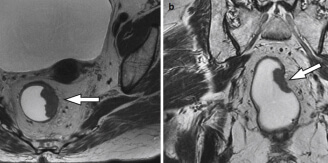

Більшість хвороб можуть призвести до смерті, тому боятися лише раку – це неприпустима помилка. Подивіться знімки органів людей, у яких все почалося з неприємного запаху з рота, сверблячки та кров'янистих виділень із анального отвору відповідно, а закінчилося доповіддю патологоанатома.